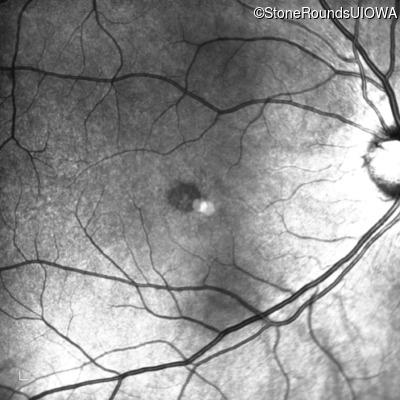

Infrared Fundus Photograph - Left - 20/40

Exemplar